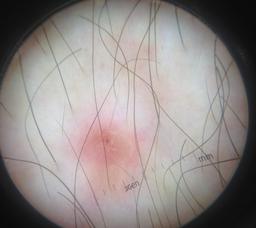

Skin lesion datasets provide essential information for understanding various skin conditions and developing effective diagnostic tools. They aid the artificial intelligence-based early detection of skin cancer, facilitate treatment planning, and contribute to medical education and research. Published large datasets have partially coverage the subclassifications of the skin lesions. This limitation highlights the need for more expansive and varied datasets to reduce false predictions and help improve the failure analysis for skin lesions. This study presents a diverse dataset comprising 12,345 dermatoscopic images with 40 subclasses of skin lesions, collected in Turkiye, which comprises different skin types in the transition zone between Europe and Asia. Each subgroup contains high-resolution images and expert annotations, providing a strong and reliable basis for future research. The detailed analysis of each subgroup provided in this study facilitates targeted research endeavors and enhances the depth of understanding regarding the skin lesions. This dataset distinguishes itself through a diverse structure with its 5 super classes, 15 main classes, 40 subclasses and 12,345 high-resolution dermatoscopic images.

Yilmaz, A., Yasar, S.P., Gencoglan, G. et al. DERM12345: A Large, Multisource Dermatoscopic Skin Lesion Dataset with 40 Subclasses. Sci Data 11, 1302 (2024). https://doi.org/10.1038/s41597-024-04104-3